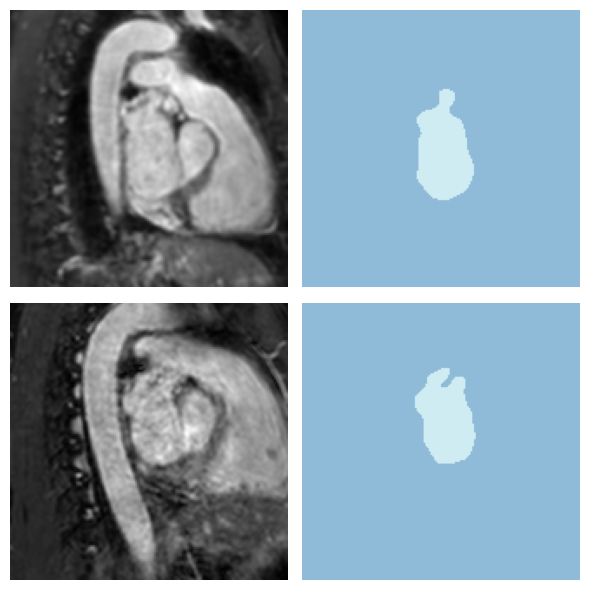

from fastMONAI.vision_plot import show_segmentation_comparison

idx = 0

val_img = MedImage.create(

val_img_paths[idx],

apply_reorder=patch_config.apply_reorder,

target_spacing=patch_config.target_spacing

)

val_gt = MedMask.create(

val_mask_paths[idx],

show_segmentation_comparison(

image=val_img,

ground_truth=val_gt,

prediction=predictions[idx],

metric_value=results_df.iloc[idx]['dsc'],

voxel_size=patch_config.target_spacing,

anatomical_plane=2 # axial view